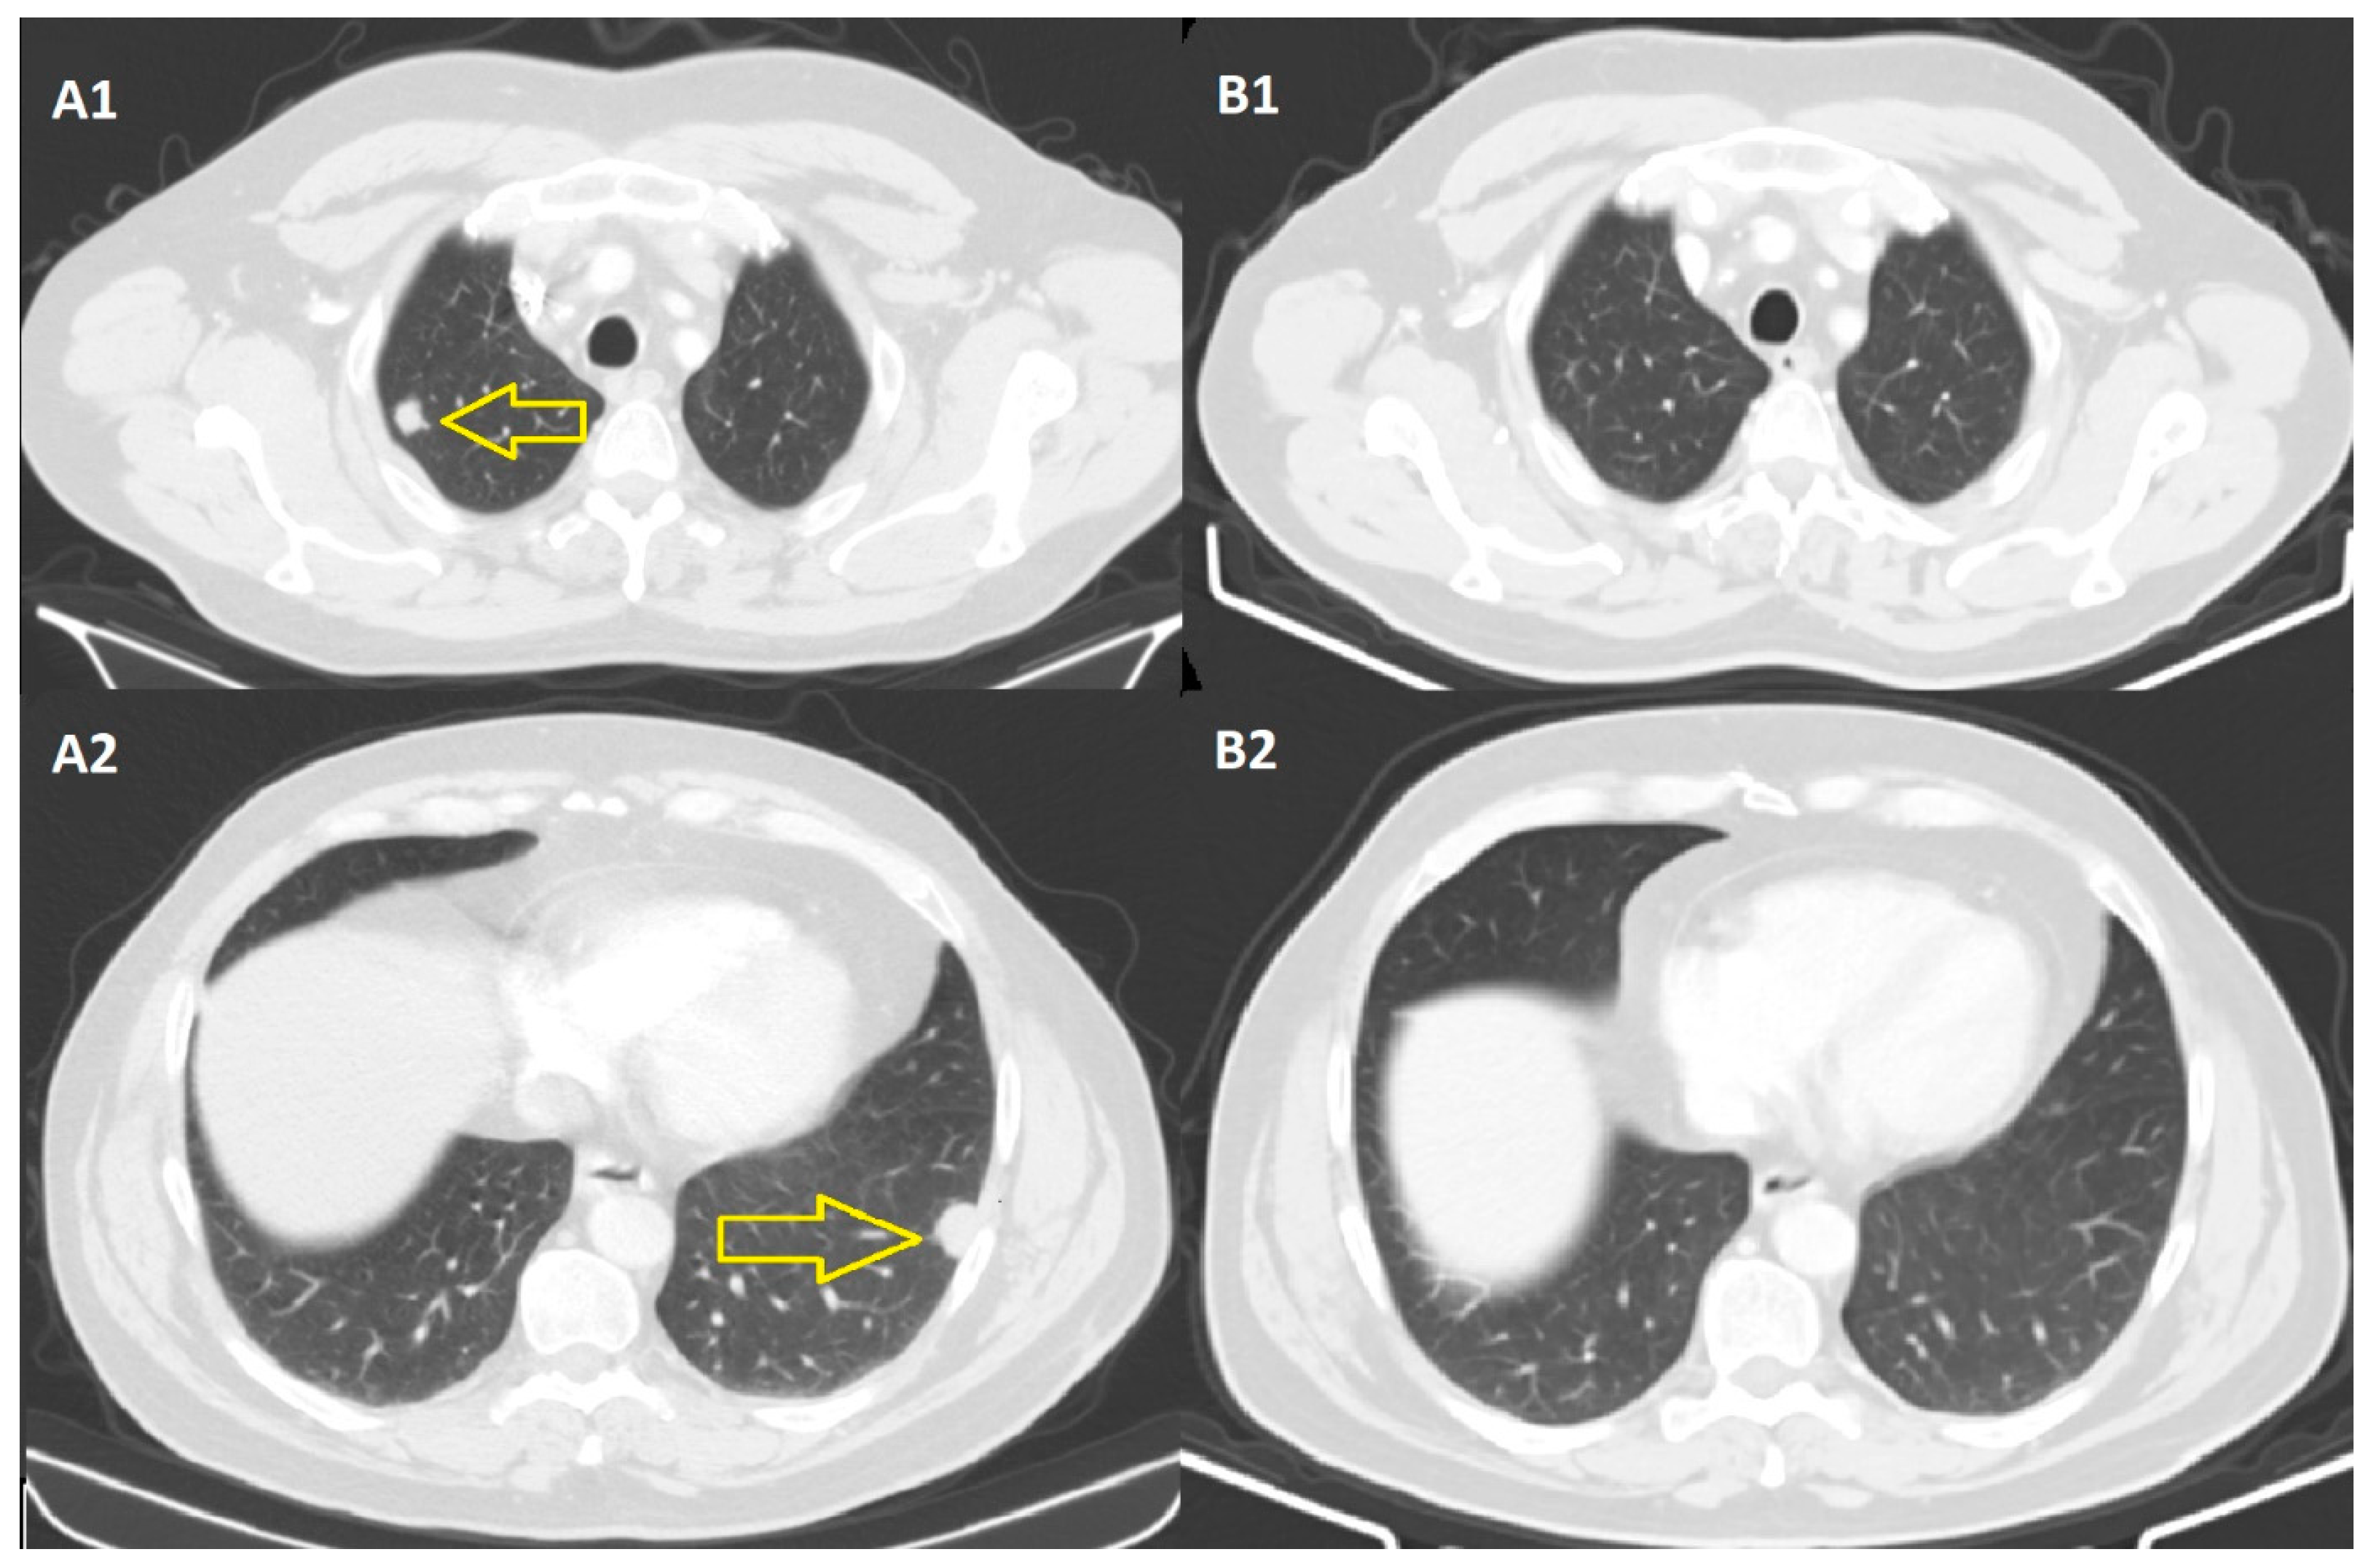

2.2. At the Thoracic Level

- The complete remission of pulmonary and lymph node metastases, 9 months after the initiation of immunotherapy, is a durable remission, with a duration of 24 months, in September 2023.